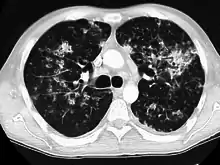

A case of miliary tuberculosis in an 82-year-old woman:

CT, 16 days after onset, showing extensive pulmonary parenchymal involvement consisting of irregular septal thickenings with ground-glass areas and centrilobular nodules with a peri-lymphatic distribution.